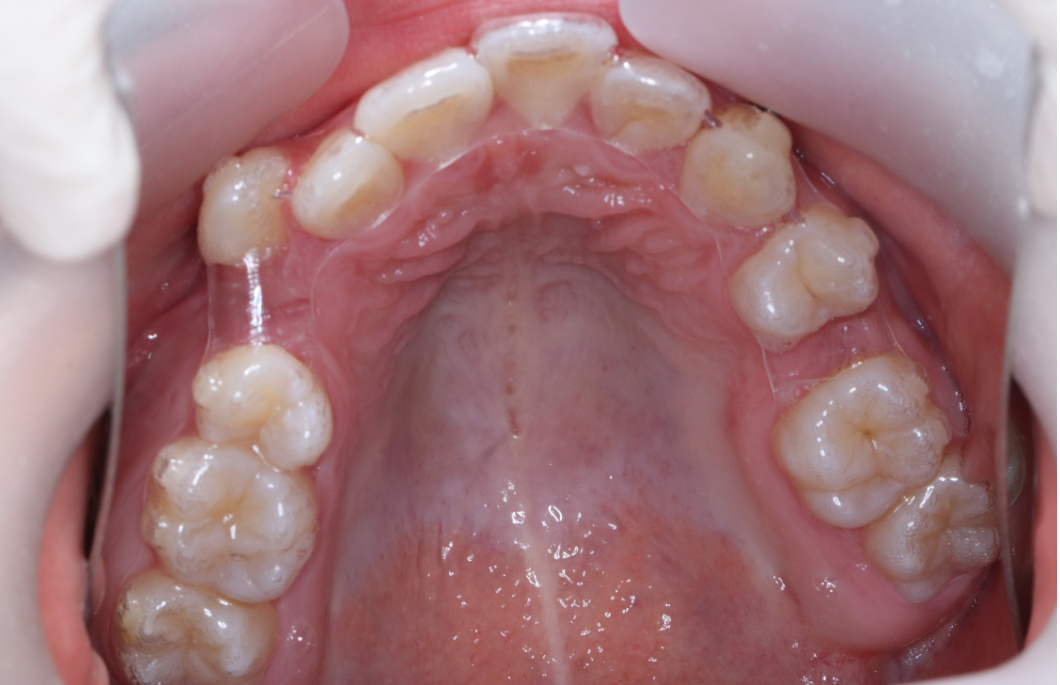

治疗前                        治疗后

无托槽隐形矫治技术

儿童错合畸形早期矫治是阻断影响儿童颌骨、牙齿正常发育的因素,促进颌面部正常发育,降低II期矫正的难度,减少II期矫正的时间,甚至不需要II期矫正。让孩子早期获得自信,绽放灿烂笑容。

术前→术后